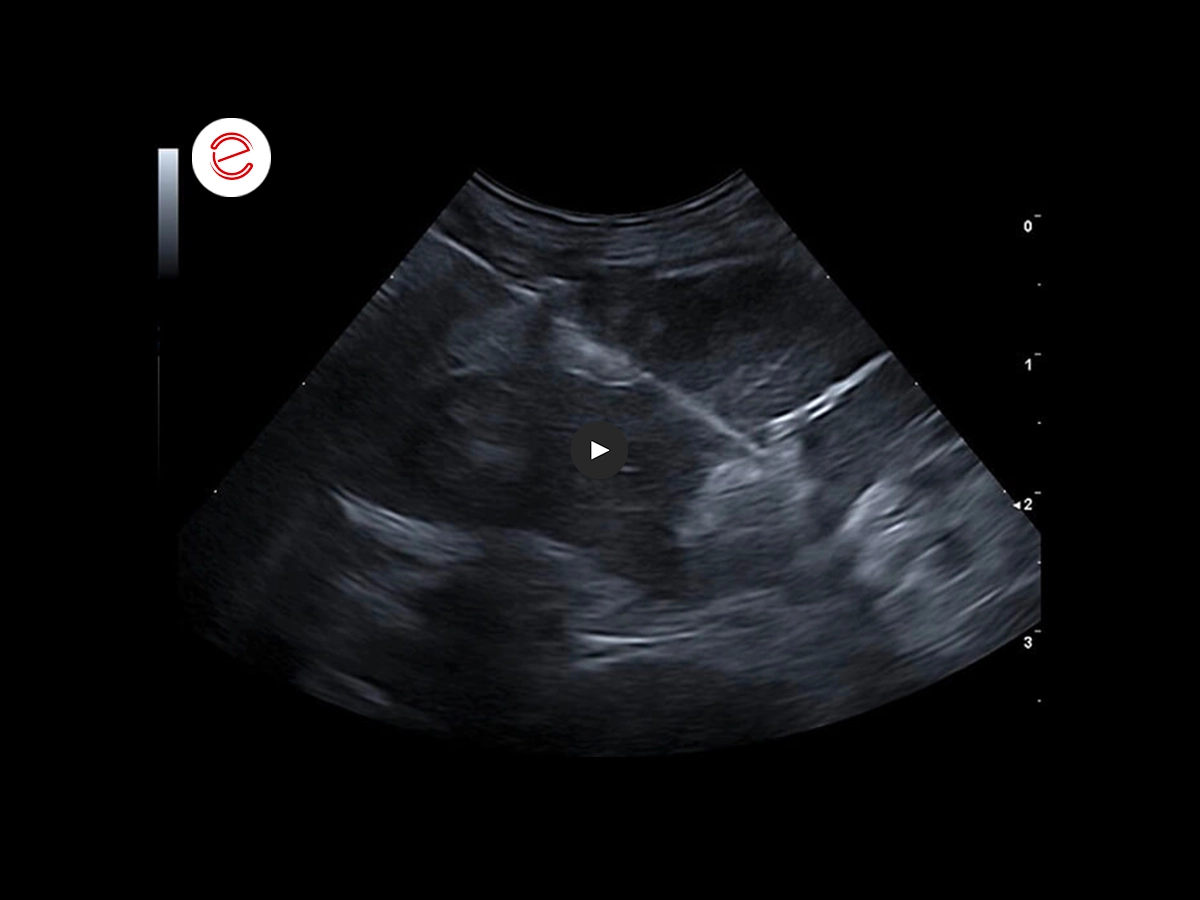

Questa immagine ecografica mostra la stratigrafia fisiologica di un’ansa digiunale, che presenta 5 strati.

Questa immagine ecografica mostra la stratigrafia fisiologica di un’ansa digiunale, che presenta 5 strati.